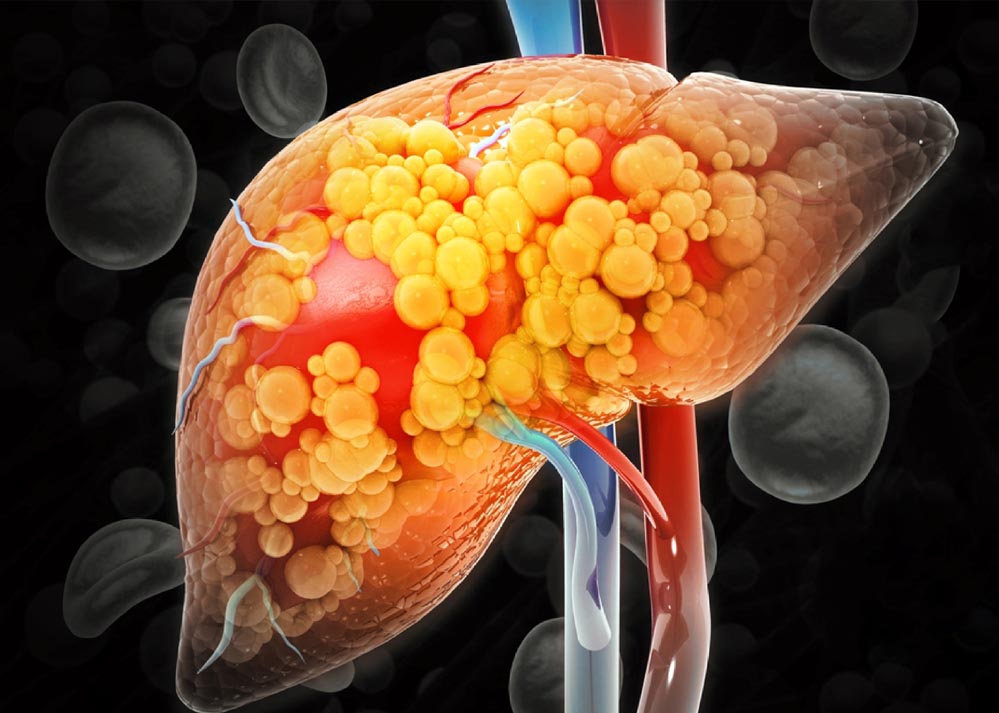

आइसक्रीम, डाइट सोडा, च्युइंग गम और अन्य शुगर-फ्री प्रोडक्ट ऐसे होते हैं जो हर उम्र के लोगों को पसंद होती हैं. मार्केट में हों या फिर मॉल में, ये चीजें काफी आसानी से उपलब्ध हो जाती हैं. एक नई स्टडी के मुताबिक, इन शुगर-फ्री आइटम्स में कृत्रिम मिठास के लिए सोर्बिटोल का उपयोग होता है जो लिवर के लिए खतरनाक होता है और फैटी लिवर डिजीज का जोखिम बढ़ा सकता है. इस स्टडी ने इन चीजों का इस्तेमाल करने वाले लोगों के मन में सवाल पैदा कर दिया है.

European Medical Journal में पब्लिश हुई स्टडी के मुताबिक, शुगर-फ्री या डाइट प्रोडक्ट में जो सोर्बिटोल होता है, उस स्वीटनर को छोटी आंत में ठीक से तोड़ नहीं पाती जिससे यह लिवर में जाकर फैट जमने की प्रोसेस को बढ़ा देता है और लिवर की कार्यक्षमता को प्रभावित करता है.

एक्सपर्ट्स का कहना है कि ये स्वीटनर सीधे तौर पर तो नहीं लेकिन लंबे समय तक सेवन करने पर नॉन-अल्कोहॉलिक फैटी लिवर डिजीज (NAFLD) का खतरा बढ़ा सकते हैं.

रिसर्च कहती है जो रोजाना लगभग 1 कैन डाइट सोडा या शुगर-स्वीटेड ड्रिंक पीने से नॉन-अल्कोहॉल फैटी लिवर डिजीज को जोखिम बढ़ जाता है. ये खतरा डाइट सोडा से लगभग 60% और शुगर ड्रिंक से 50% अधिक होता है. इसलिए एक्सपर्ट सलाह देते हैं कि पानी या बिना स्वीटनर वाले लिक्विड्स का सेवन करना अधिक सुरक्षित और हेल्दी होता है.

रिसर्च में सामने आया है कि हेल्दी आंतों के बैक्टीरिया सोर्बिटोल को तोड़ते हैं लेकिन जब ये बैक्टीरिया कम हो जाते हैं या संक्रमित हो जाते हैं, तब सोर्बिटोल का शरीर में जमाव होना शुरू हो जाता है.

यह सोर्बिटोल सीधे लिवर तक पहुंचकर वहां फैट के जमाव का कारण बनता है जिससे नॉन-अल्कोहॉलिक फैटी लिवर डिजीज का खतरा बढ़ जाता है. इससे पहले की यह बीमारी आमतौर पर शराब से जुड़ी जानी जाती थी, लेकिन अब यह नॉन-अल्कोहॉल फैटी लिवर डिजीज के रूप में अधिक सामान्य हो गई है.

डाइट सोडा और अन्य कम चीनी या शुगर-फ्री ड्रिंक्स के सेवन से भी लिवर की समस्याएं हो सकती हैं क्योंकि इनमें इस्तेमाल होने वाले आर्टिफिशियल स्वीटनर्स और सोर्बिटोल, आंत के बैक्टीरिया के संतुलन को बिगाड़ सकते हैं.

यह न केवल लिवर फैट को बढ़ाता है बल्कि मेटाबोलिक सिंड्रोम, टाइप 2 डायबिटीज और दिल की बीमारियों के जोखिम को भी बढ़ा सकता है. एक्सपर्ट्स का कहना है कि शुगर-फ्री ऑपशंस हमेशा हेल्दी नहीं होते, बल्कि इनसे लिवर डिजीज का जोखिम भी हो सकता है.

आइसक्रीम, डाइट सोडा और च्युइंग गम जैसी चीजों में उपयोग हो रहे सोर्बिटोल और अन्य आर्टिफिशियल स्वीटनर्स लिवर की हेल्थ के लिए हानिकारक हो सकते हैं, जिससे इनके सेवन को सीमित करना चाहिए.